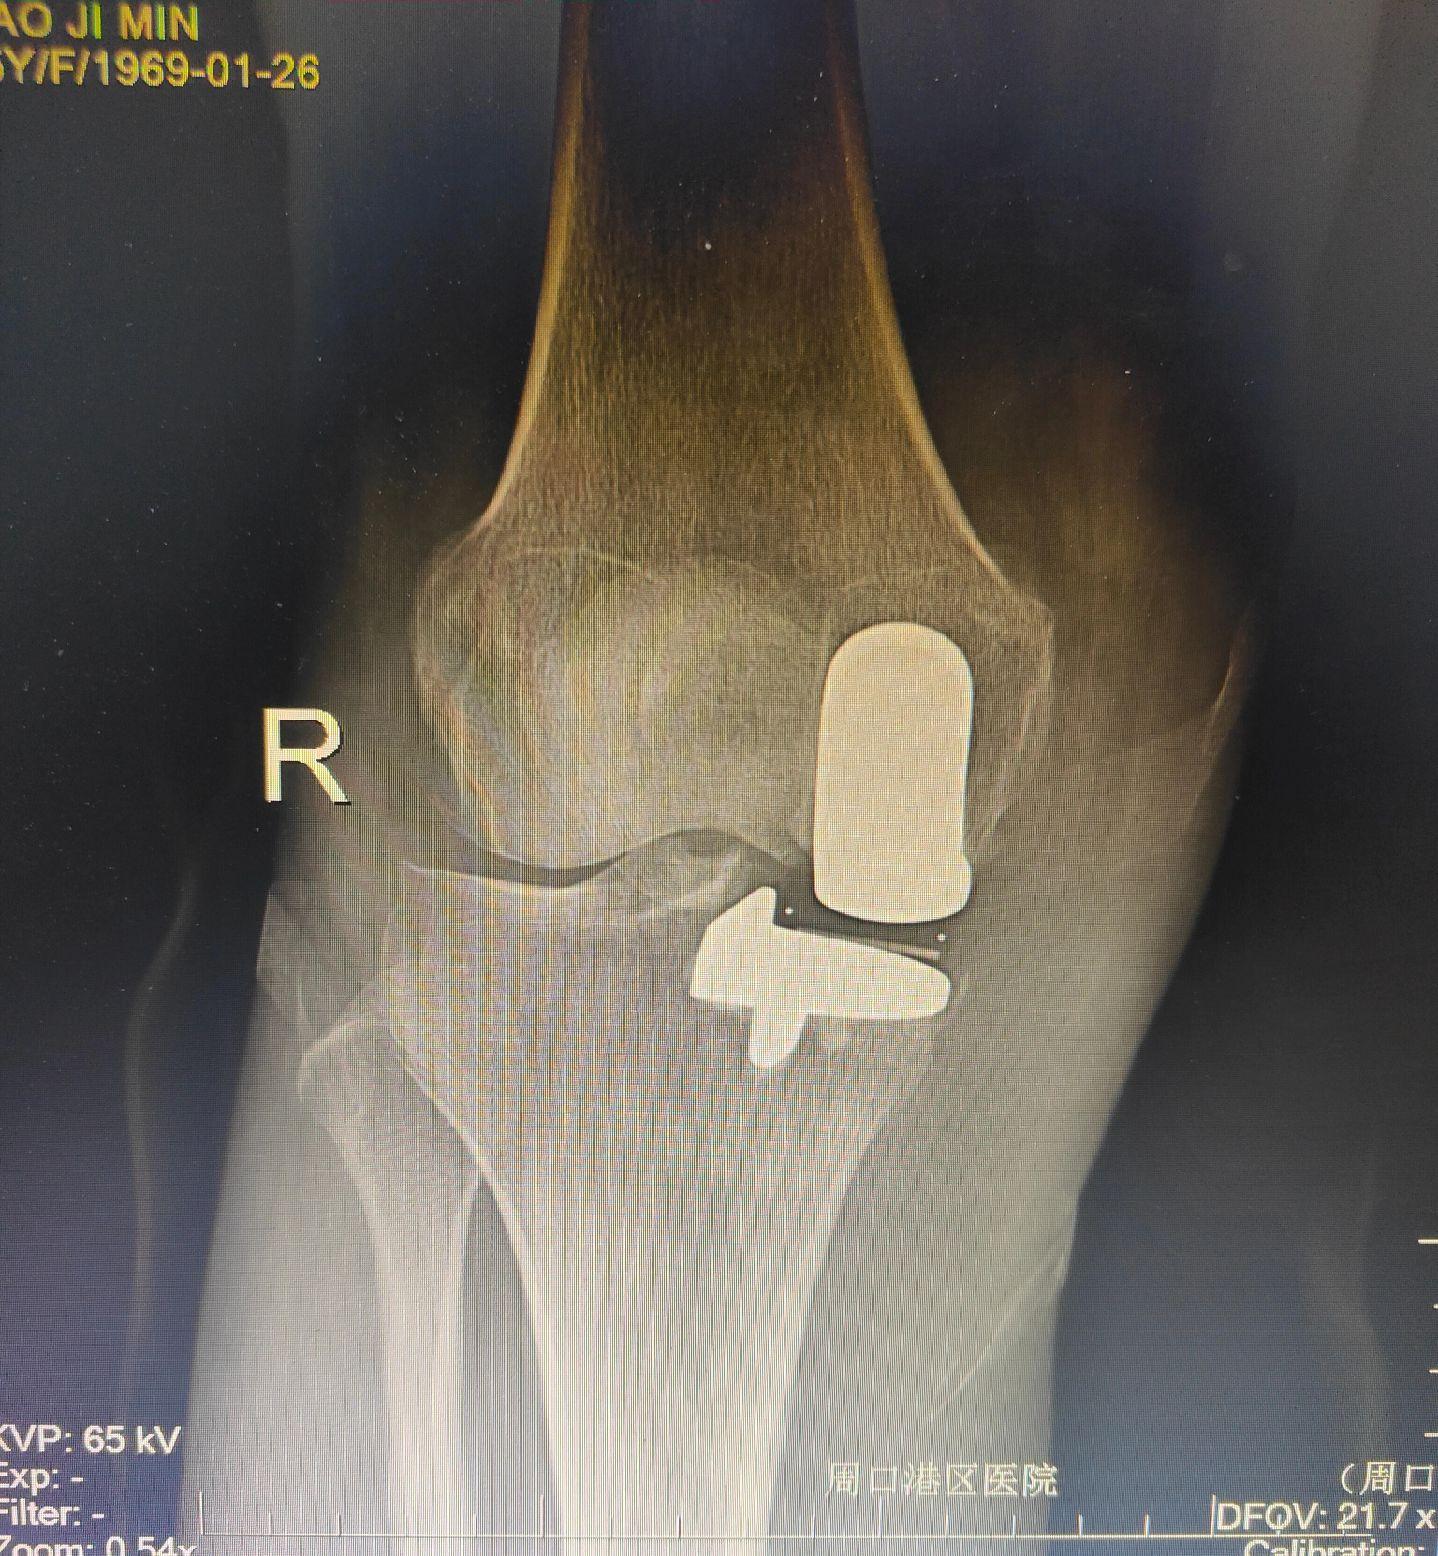

单髁置换术。(看图猜假体)每款假体都有自己的优点,不要单纯追求国产或进口,也不要单纯追求活动平台或固定平台,适合自己才是最好的。愿每一位病人都能快速顺利康复🌹